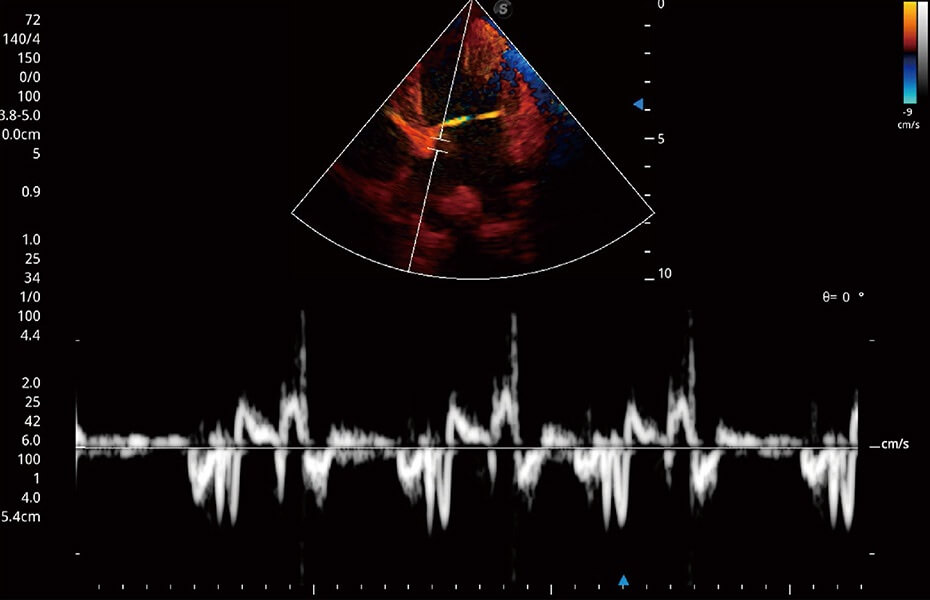

ProPet 60 作為一款高端臺(tái)式動(dòng)物超聲設(shè)備,為動(dòng)物醫(yī)生的日常診斷提供了一系列貼合動(dòng)物臨床需求、解決臨床實(shí)際問題的高級(jí)成像功能。憑借全系列高清探頭,滿足醫(yī)生對(duì)腹部、心臟、生殖、淺表、肌骨等成像的所有需求,切實(shí)幫助您提升檢查效率,提高診斷信心。